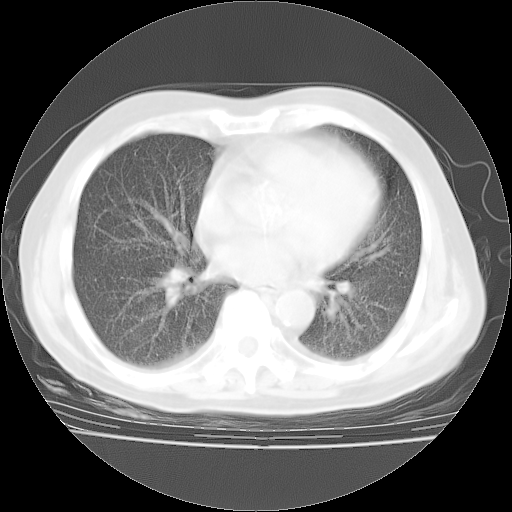

4月28日肺部CT